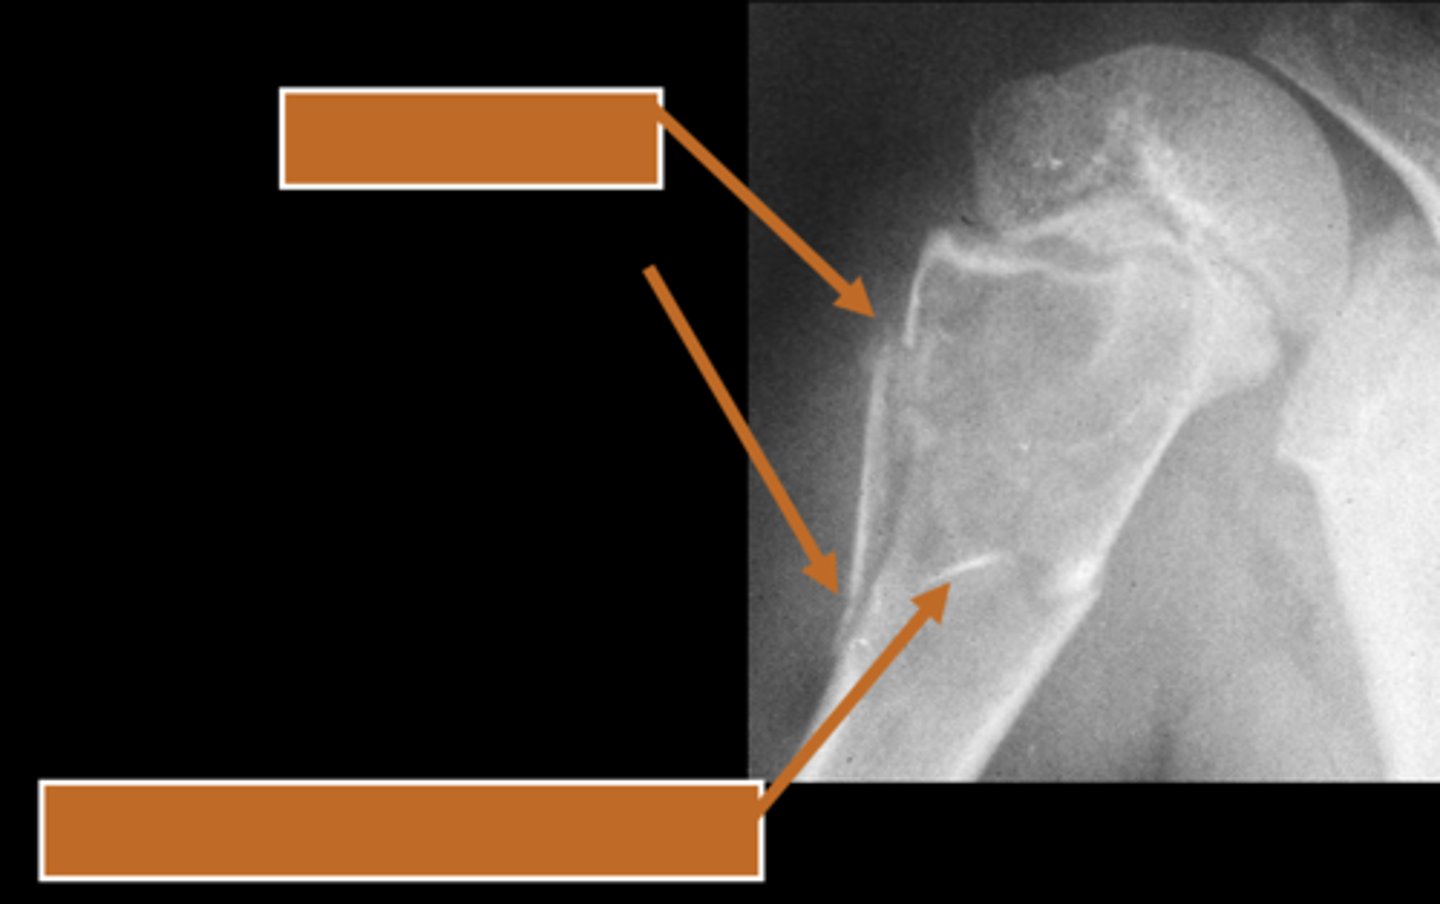

Aneurysmal bone cyst

- 1% of biopsied primary bone tumors

- M:F, 2:3

- 5-20 y.o.

- Acute pain

- Previous trauma

- 80% tubular bones and spine

- Eccentric

- Metaphyseal

- Osteolytic with fine trabeculae

- Saccular ballooning of cortex

- May cross epiphysis

- Periosteal buttressing

State the radiographic features of aneurysmal bone cyst in tubular bones